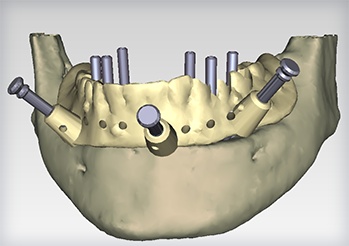

Computer-Guided Surgery

Computer-guided surgery, with the aid of modern and increasingly sophisticated software, enables the surgeon to plan the operation by means of a computer program, step by step, starting from a proper dental CT scan. It also allows very accurate transformation of this virtual surgery to a non-traumatic and micro-invasive real surgery.

After the 3-D CT scan of the dental area to be treated is completed, this scan will be imported into a highly technological software program that will elaborate two- and three-dimensional anatomical structures, enabling us to carry out a virtual computer simulation. We plan the implant placement and prosthetic structure precisely to a tenth of a millimeter. Other additional advantages of this method are the possibility of preventing surgical risk, the speed of this operation, and the rehabilitation period of the patient without the impact characteristics of traditional techniques.